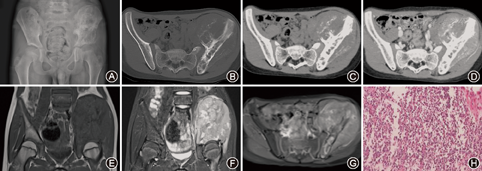

骨质改变:13例中9例表现为单纯溶骨性破坏,4例为混合型(图1A、图2A),其中3例肿瘤内见絮状骨化,1例为针状;4例见骨质膨胀性破坏,2例见骨性分隔,2例见骨皮质中断,6例见局部骨质硬化。3例见骨膜反应。软组织肿块:6例可见。

骨质改变:13例中3例表现为单纯溶骨性破坏,10例为混合型,其中8例肿瘤内絮状骨化,2例为针状,骨化较少;10例见骨质膨胀性破坏,3例见骨性分隔,12例见骨皮质中断,11例见局部骨质硬化。骨膜反应:10例可见,其中5例为层状并见Codman三角,5例为放射状。软组织肿块:13例均可见,呈等或稍低密度,其中5例边界较清晰,4例周围软组织受压。5例见不完整的骨包壳(图1B,图1C,图1D、图2B,图2C,图2D)。4例增强扫描后不均匀强化(图1D、图2D)。

骨质改变:13例中均见明显骨质破坏,T1WI为低信号,T2WI为混杂高信号,骨髓水肿,边界模糊。肿瘤内骨化显示欠清。骨膜反应:显示模糊,2例见放射状骨膜反应,5例见层状骨膜反应,T1WI及T2WI均为低信号。软组织肿块:13例均可见,病变范围大于CT和X线平片,T1WI呈等或低信号,T2WI呈混杂高信号,其中5例见斑片长T1长T2信号区(病理为液化坏死),8例软组织肿块边缘清晰,9例肿块边缘见不完整的线样低信号(病理为假包膜),周围软组织局部受侵(图1E、图1F,图2E、图2F)。10例见软组织肿块周围水肿信号。4例MRI增强扫描后不均匀强化(图1G,图2G、图2H)。

大体标本5~15 cm,肿瘤软、脆,呈粉红或灰白色伴有骨质破坏及软组织肿块,5例可见液化坏死区,呈半流体状。9例可见不完整假包膜。镜下可见均匀一致的小圆形未分化肿瘤细胞,胞质少,细胞边界不清,胞核圆形,染色质呈斑点状(图1H)。免疫组化CD99(+)13例,CD56(+)、PAS(+)、Vim(+)各11例,Ki-67(+)10例,S-100(+)、NSE(+)各5例、Syn(+)3例、CgA(+)2例。